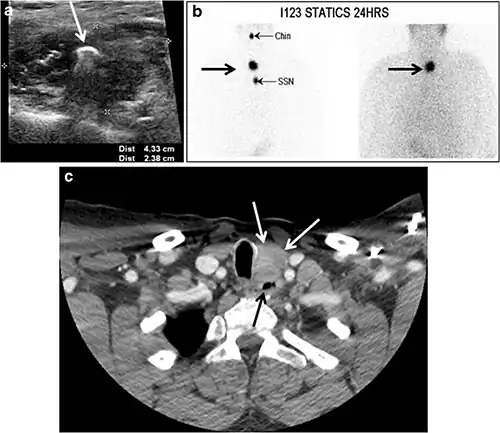

Fig. 7. A 51-year-old female patient post total thyroidectomy for PTC with elevated thyroglobulin measurement. an Axial non-enhanced CT scan of the neck at the level of the thyroid bed demonstrates a well-defined, rounded, homogenously dense soft tissue situated between the trachea and left internal jugular vein (white arrow). b Transverse ultrasound image of the neck demonstrates a well-defined, homogeneous, hypoechoic soft tissue nodule measuring 6 mm (white arrow) with no detected micro-calcifications. Biopsy showed a predominantly residual normal thyroid tissue with micro-foci of PTC.[1] -

Fig. 8. A 48-year-old male patient post total thyroidectomy with PTC recurrence. a Transverse greyscale ultrasound of the neck demonstrates a left thyroid bed heterogeneous, predominantly hypoechoic irregular lesion with calcifications (white arrow). b A spot image of iodine 123 total body scan of the neck demonstrate a focus of abnormal radiotracer uptake at the left thyroid bed (Black arrows) between the annotated markers. c Enhanced axial CT scan of the neck demonstrates an enhancing large left thyroid bed mass (white arrow) with no calcifications. The lesion exerts a mass effect on the oesophagus (black arrow) and is inseparable from the trachea.[1] -

Fig. 9. A 58-year-old male patient with persistence PTC at thyroid bed with hypervascular nodal metastasis. a–c Transverse greyscale and colour Doppler neck ultrasound demonstrate hypoehoic soft tissue in the left thyroid bed (white arrow in a). There are a heterogeneous enlarged lymph nodes at level 2 and 3 with markedly increased vascularity (white arrow in b and c). d–f Enhanced axial CT images of the neck demonstrate a 2.7 × 1.4 cm hypodense soft tissue lesion anterior to the left carotid sheath (white arrow). There are left-sided enhancing abnormal and enlarged lymph nodes at cervical level 2 and 3 (black arrows).[1]